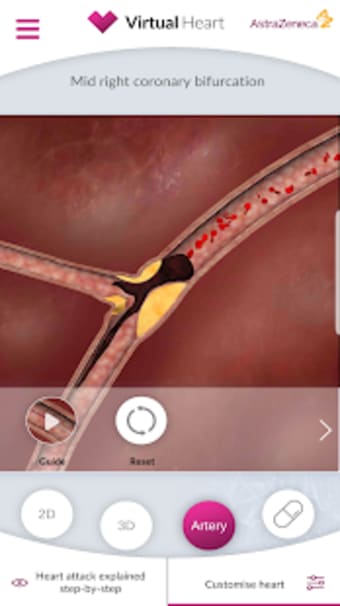

Virtual Heart - ANZ är en gratis programvara för Android, som ingår i kategorin 'Medical'.Om Virtual Heart - ANZ för Android